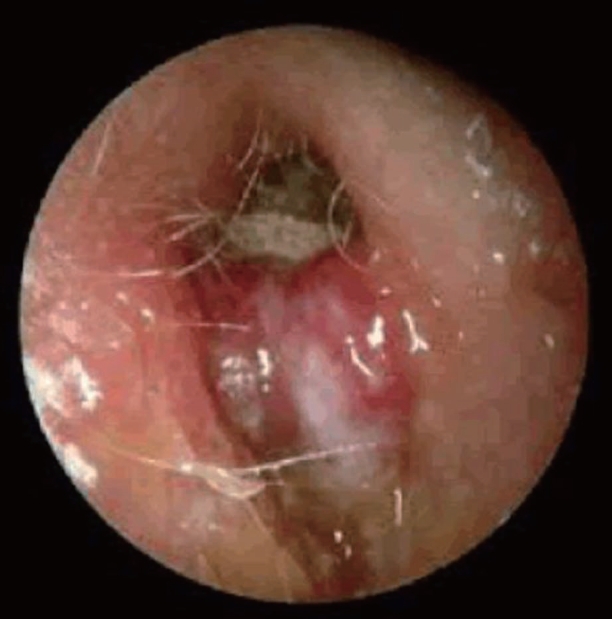

67세 남환이 2달 전부터 지속된 우측 이루를 주소로 내원하였다. 환자는 이전에는 이루를 경험한 적이 없으며, 2달간 인근 병원에서 항생제 치료를 받았으나 큰 호전이 없었다고 한다. 환자는 심한 통증으로 밤에는 잠들기 어렵다고 호소하였으며, 현재 고혈압과 당뇨로 약물 복용 중이나 혈당이 잘 조절되지 않는다고 한다. 다음은 환자의 고막 소견이다. 해당 질환에 대해 옳지 않은 것은?